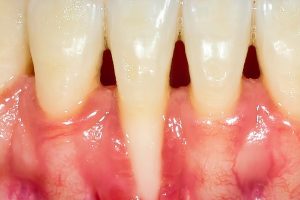

Gum recession happens when your gum tissue pulls away from your teeth and exposes the